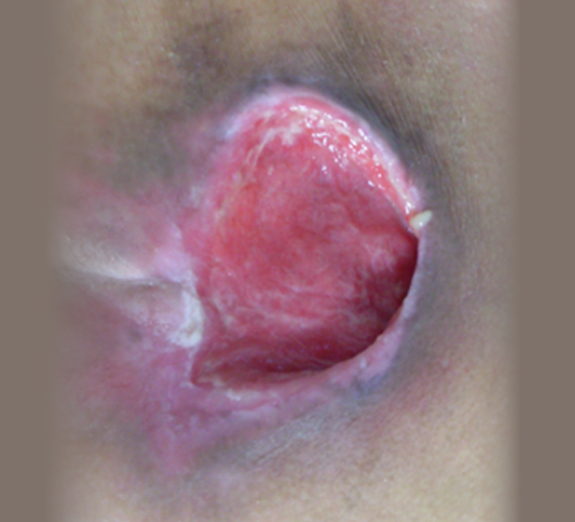

심부욕창 치료 사례

• 치료 전

• 치료 후